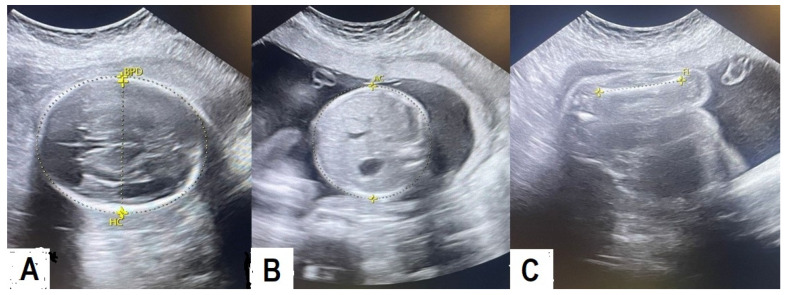

Methods: In this retrospective study, electronic records of 270 newborns who fulfilled the inclusion criteria were retrieved. A structured data sheet was used to collect the EFW, calculated by the Hadlock A formula using real-time ultrasound imaging on the day of delivery or the day before, and the actual BW immediately after delivery.

Results: Out of 270 fetuses, 53.7% (145) were female, and 46.3% (125) were male. The mean BW was 2918.1 ± 652.81 g (range: 880 to 5100). The mean EFW was 3271.55 ± 691.47 g (range: 951 to 4942). The mean gestational age was 38 ± 2.48 weeks (range: 29 to 42). Spearman's rho correlation test revealed strong compatibility between EFW and BW (r = 0.82, p < 0.001). Linear regression analysis showed a strong correlation between EFW and BW (R = 0.875, R2 = 0.766, and p < 0.001). The cross-tabulation test showed 86.8%, 78.4%, and 26.9% compatibility between measurements of EFW and the true BW in group-1 (<2500 g), group-2 (2500-4000 g), and group-3 (>4000 g) fetuses (p< 0.001).